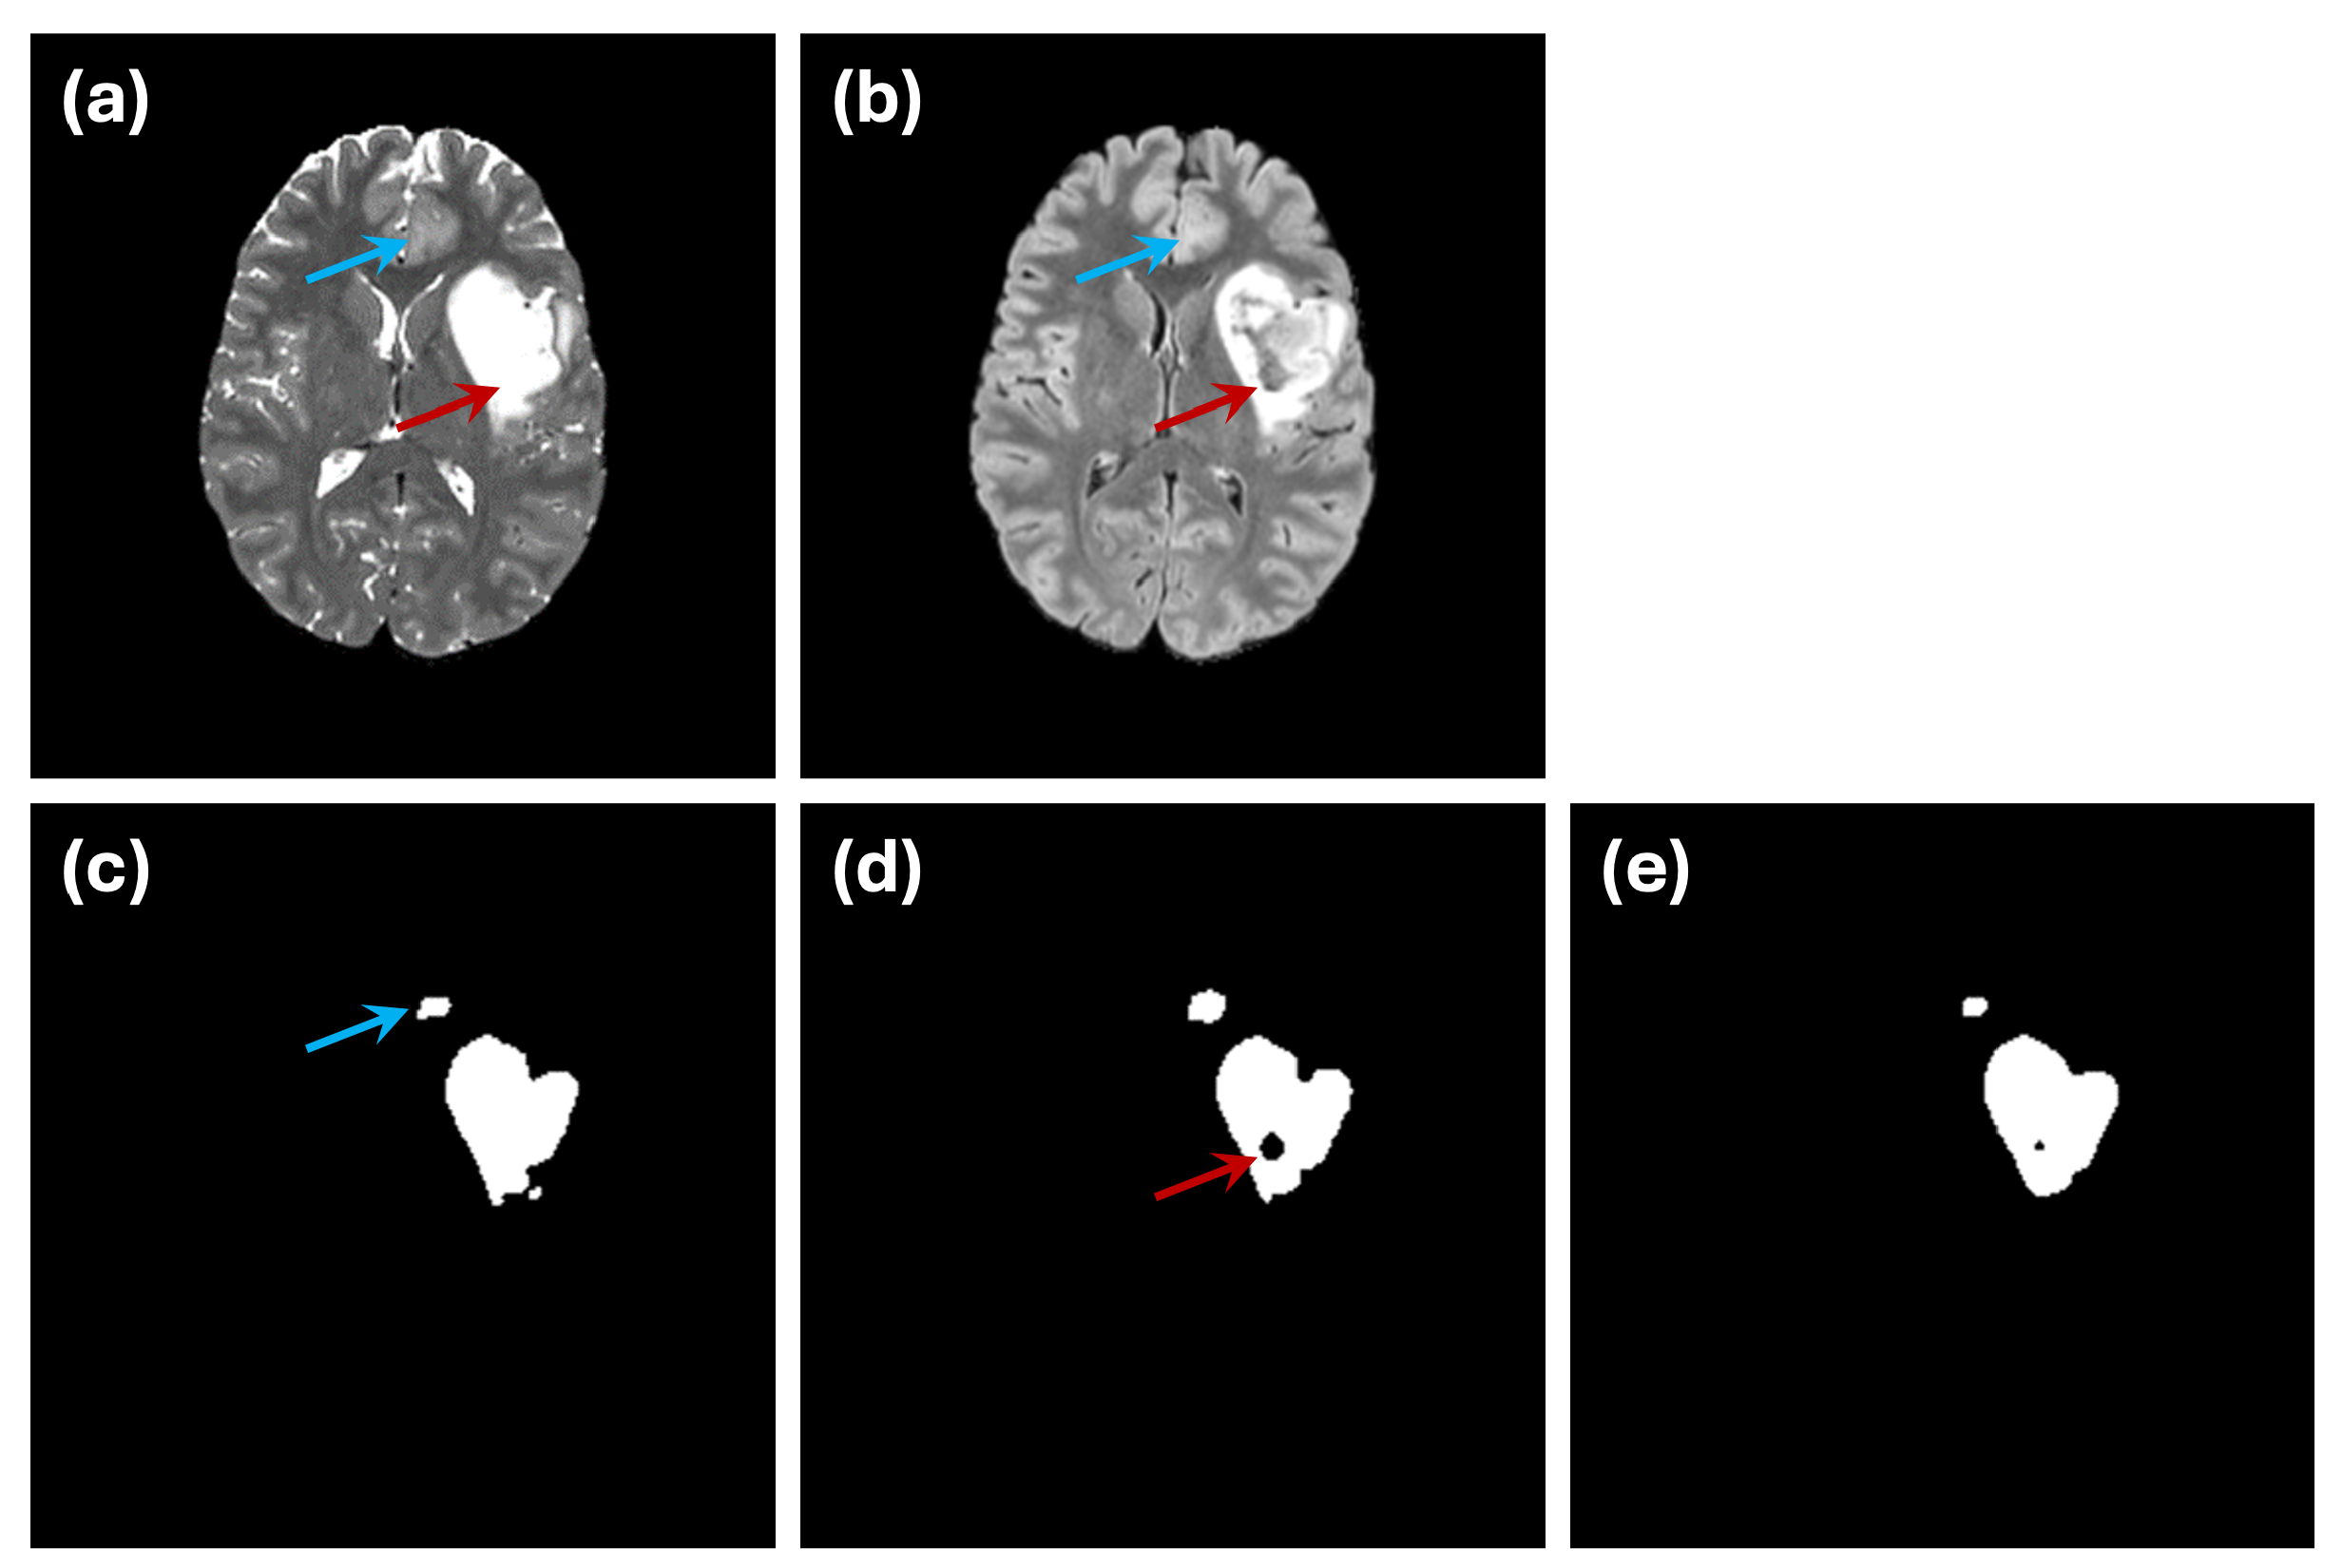

4.2. Performance of Mutual Attention

5.3. Limitations